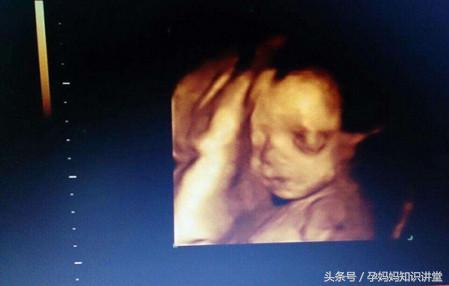

四维彩超提供了包括腹部、血管、小器官、产科、妇科、胎儿彩超图泌尿科、新生儿和儿科等多领域的多方面的应用。其结果是:能够显示您未出生的宝宝的实时动态活动图像,或者其它人体内脏器官的实时活动图像。